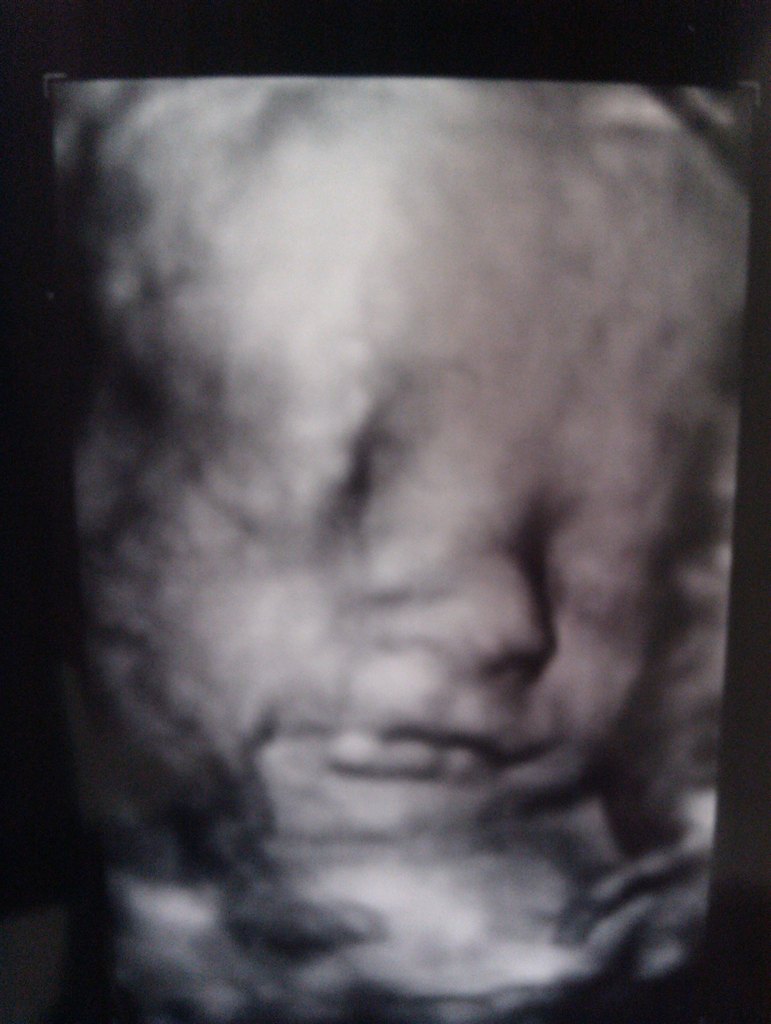

Var til 3D-scanning i uge 31 og der fik vi så bekræftet at lillemanden ikke er så lille igen. Han vejede 1722 g, så han var lidt større end gennemsnittet. 8 dage før havde min JM + en studerende skudt ham til kun 1100-1200, hvilket jeg også syntes var lidt lavt. Men alt i alt, så er han en fin størrelse.

Det var svært at få super gode billeder af ham til scanningen, da han lå helt tæt op ad moderkagen og puttede, og på den anden side nussede han med navlesnoren. Men sød ser han nu ud.